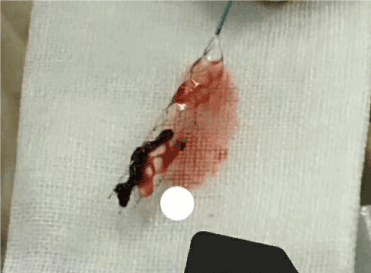

Endovascular thrombectomy: microcatheter through the occluded artery, micro catheter trace imaging showed again in the arterial lumen, distal blood flow is good, as shown in Figure 4. Then, according to the diameter of the lesion, the SolitaireAB 4 mm×20 mm or SolitaireAB 6 mm×20 mm (EV3, Inc, USA) was placed in the lesion, as shown in Figure 5. The stent and microcatheter were then removed simultaneously to the guide tube, and the catheter was removed from the body, and the thrombus extracted by the Solitaire stent was examined, as shown in Figure 6. If necessary, take the bolt several times, and then check the angiogram to see if the blood vessel is Complete recanalization after the thrombus is completed (Figure 7).

Figure 6. Stent removed thrombus

Figure 7. Basilar artery and its branches were unobstructed